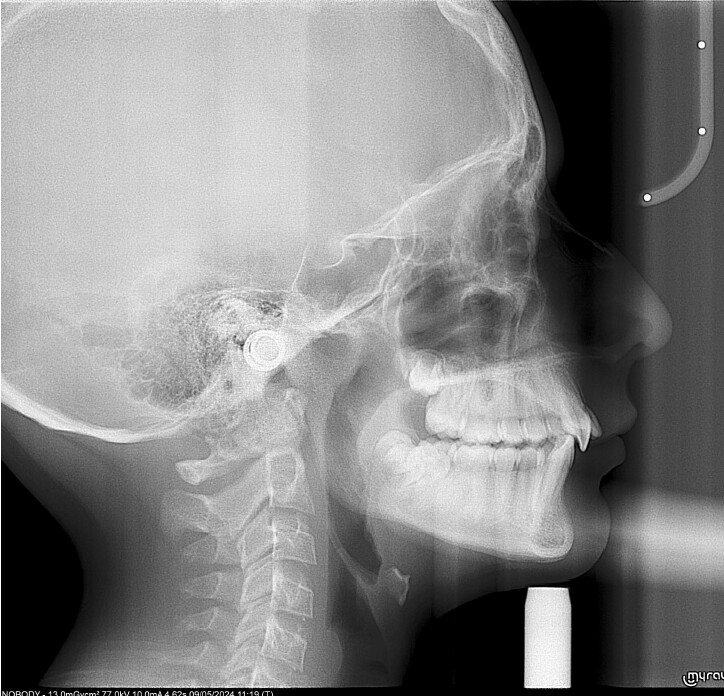

Um paciente do sexo masculino, com 13 anos de idade, apresentou-se com uma mordida profunda, caracterizada pela cobertura quase completa dos incisivos mandibulares. A avaliação clínica revelou apinhamento em ambas as arcadas, rotações dentárias e proclinação dos incisivos laterais superiores, contribuindo para as preocupações estéticas do paciente. O perfil facial era retrusivo, consistente com retrognatismo mandibular, e não foram detectadas anomalias periodontais significativas.

DIAGNÓSTICO:

O paciente apresentava uma relação esquelética de Classe II com molares e caninos bilaterais em Classe II e um padrão dentário de Classe II divisão 2. A mordida profunda estava associada a um apinhamento anteroinferior e a uma curva de Spee acentuada. A análise facial revelou boa simetria, um terço facial inferior ligeiramente aumentado e um perfil convexo caracterizado por retrusão mandibular e do mento. A competência labial estava ligeiramente reduzida, com diminuição do ângulo nasolabial e leve tensão do músculo mentoniano, fatores que comprometiam a harmonia facial global.